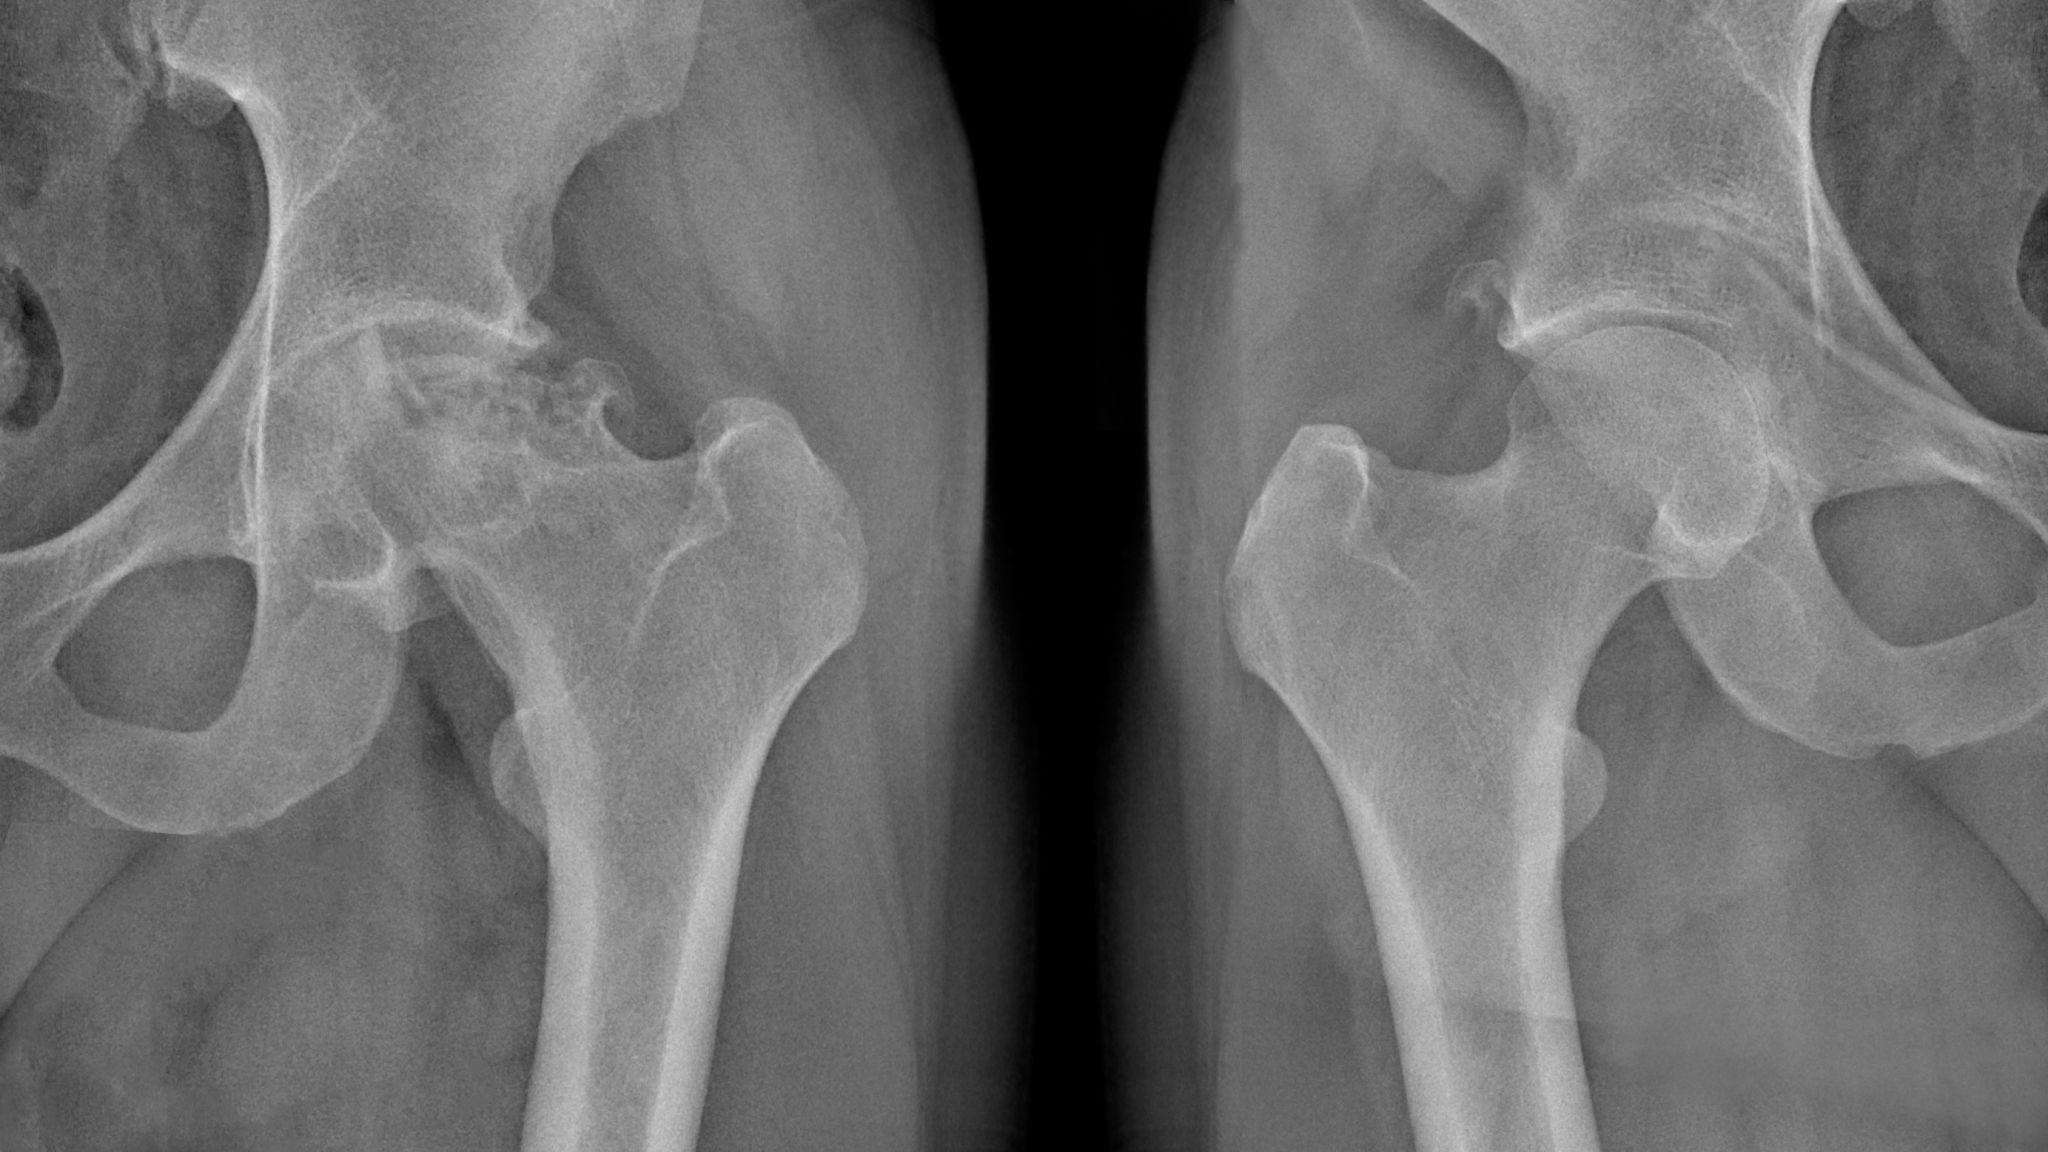

レントゲンでは骨の形や隙間の変化を見て、必要に応じてMRIなどで軟骨や関節内部の様子を確認することがあるそうです。段階的に情報を集めながら原因を絞っていく方法がとられると解説されています。

疑われる状態によって、確認の仕方も変わると言われています。たとえば変形性股関節症では可動域や歩き方の特徴が参考になることがあるそうです。